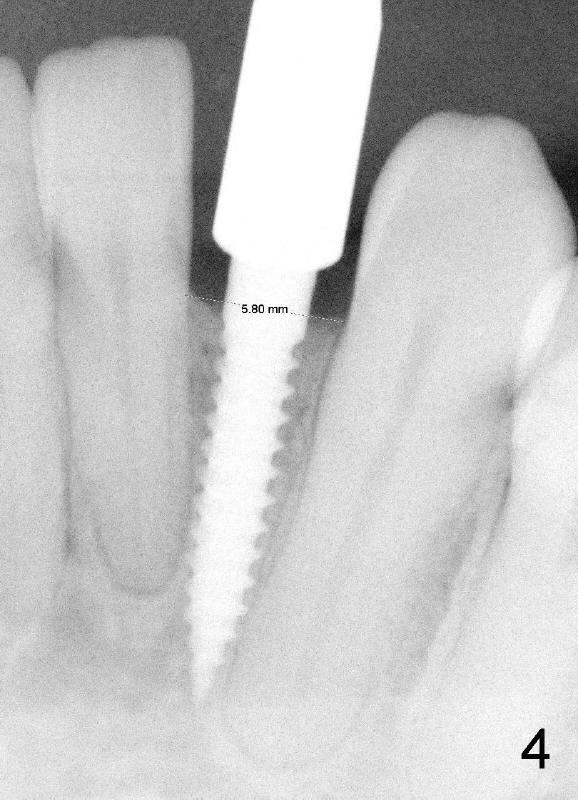

A 44-year-old black lady with ortho several years ago requests fixed restoration for #23 with narrow mesiodistal width (Fig.1). Treatment options are proposed: fixed prosthetic denture and implant. After discussion of advantages and disadvantages of each option, the patient agrees to have implant restoration. A 1.5 mm pilot drill is used to create osteotomy (Fig.2,3). After using 2.0 mm and 3.0 mm tapered osteotomes through the cortex at the crest, 3x17 mm 1-piece implant is placed (Fig.4) and temporary crown is immediately cemented with no centric or lateral occlusion. The patient is doing fine postop, although there is very mild percussion involving the tooth #24, three days postop. Fig.5 and 6 show that the temporary crown is bonded to the neighboring teeth interproximally and lingually. Retrospectively, ortho should have been done to torque the root of the tooth #22 prior to implant placement. Fig.3,4 show that there is space between #21 and 22.